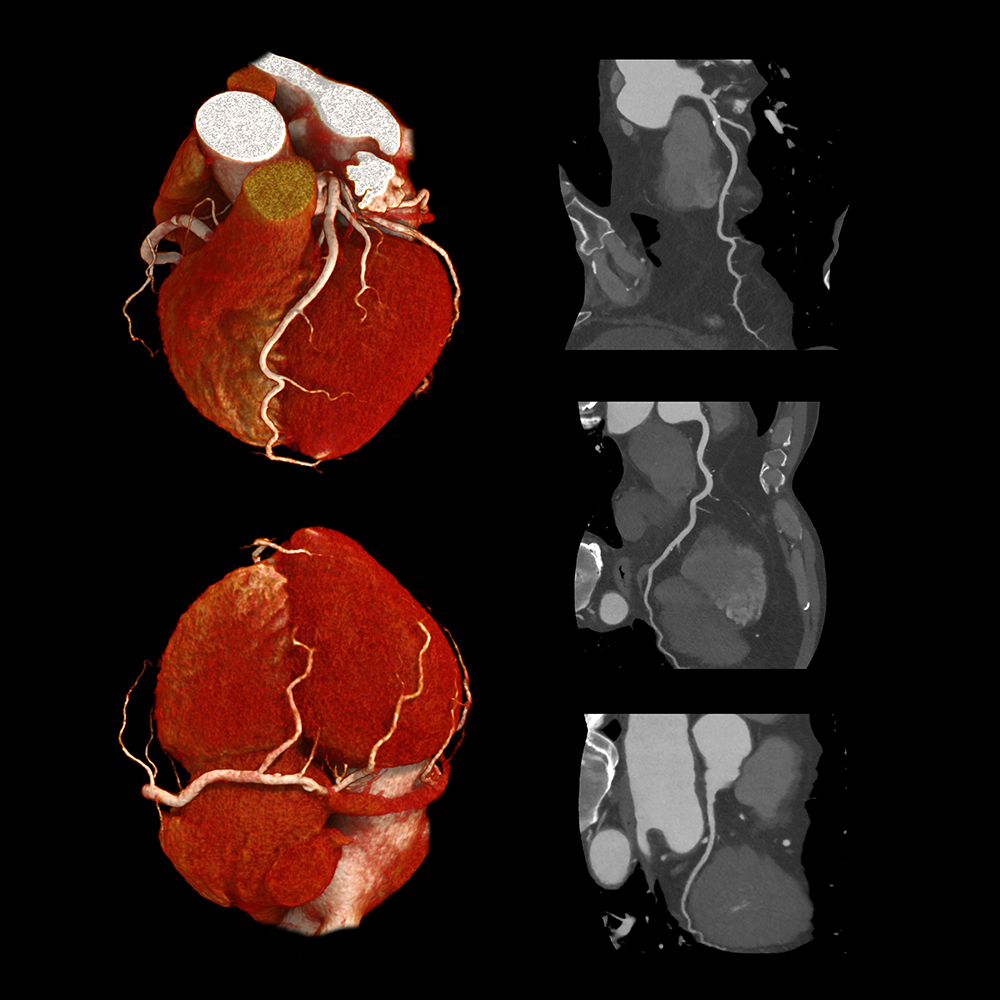

CT SCAN

img01

CT-Scan Aquilion Prime SP

• Comfortable & Fast Experience

Wide 78 cm open design and extremely fast scanning reduce stress, breath-holding, and discomfort — perfect for children, elderly, and nervous patients.

• Low Radiation for Your Safety

Advanced dose-reduction technology keeps radiation as low as possible while still delivering clear, reliable images.

• Clear & Accurate Results

High-resolution, 160-slice imaging provides sharp detail for chest, abdomen, brain, spine, blood vessels all angiographic studies (Coronary Angio) CALCIUM SCORE, full-body assessments and stroke evaluation.

• Ideal for All Patients

Comfortable for larger or mobility-impaired patients thanks to the wide opening and quick exam times.

• Great for Emergency & Routine Scans

Captures fast, precise images for trauma.

• Smooth, Quick Visit

High-speed imaging means less time on the table and faster results for your doctor.

• Vitrea post processing AI software

Multi-planer reformatting (MPR), 3D and 4D Advanced visualization, Quantitative analysis and measurement tools (Calcium score), Reduce noise and artifact.